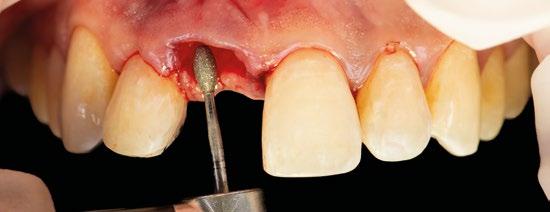

4.- Desepitelizamos en margen gingival. (Figura 17)

8.- Realizamos osteotomía mediante férula quirúrgica utilizando fresa piloto. (Figuras 22 a 24)

9.- Seguimos preparando el lecho utilizando fresado biológico con la OsseoShaperTM. (Figura 25)

10.- Colocamos implante Nobel Biocare N1TM TiUltra de 3,5x13. (Figura 26)

11.- Observamos el torque obtenido de 50N por lo tanto podemos realizar carga inmediata. (Figura 27)

12.- Colocamos aditamento N1TM Base XealTM con el fin de trabajar la prótesis a nivel gingivall. (Figura 28)